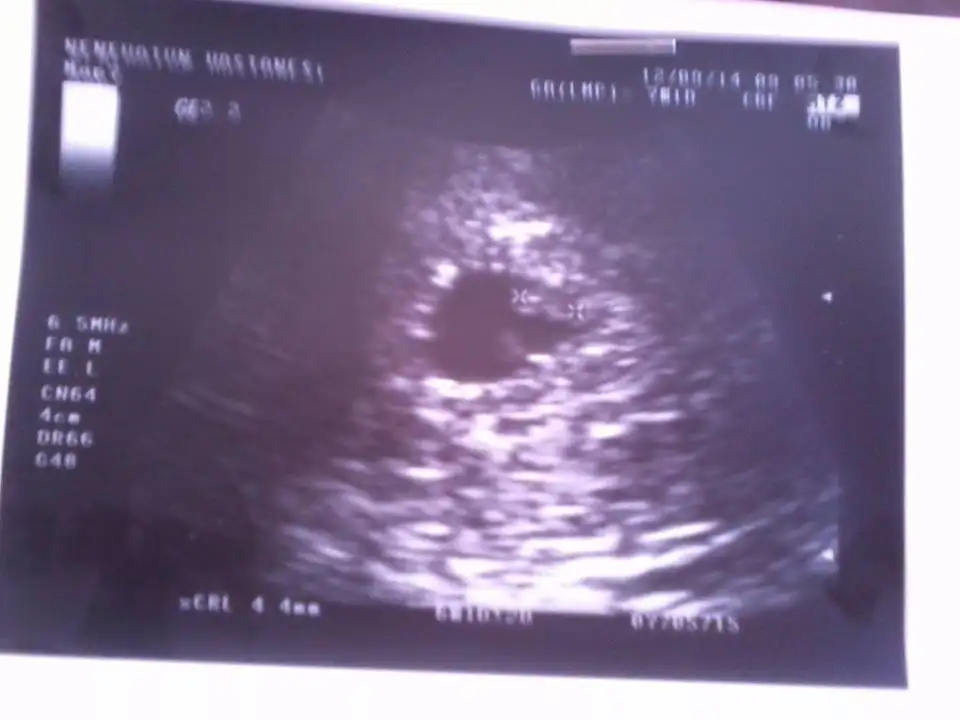

gözün aydın kalp atışlarını duymuşsun bu arada bebegin kesenin tam olarak neresinde gönderdiğin fot blu cıkmıs yukardamı kesininkızlar kalp atışlarını gördüm dr yenı geldım sımdılık bır soru yok dedı dr kan sulandırıcı iğne verdi 10 gunde 1 tane ılkını oldum rabbım korusun bizi buda yeni fotomuz

hay masallah yaaa cokk guzelkızlar kalp atışlarını gördüm dr yenı geldım sımdılık bır soru yok dedı dr kan sulandırıcı iğne verdi 10 gunde 1 tane ılkını oldum rabbım korusun bizi buda yeni fotomuz

kese yuvarlak sıyahlık var içinde ikitane artı var boy ölçümü vargözün aydın kalp atışlarını duymuşsun bu arada bebegin kesenin tam olarak neresinde gönderdiğin fot blu cıkmıs yukardamı kesinin

gözün aydın canım darısı başımıza inşallah..Merhaba anneler, biz bugun kalp atislarini gorduk bebegimizin. Darısı herkesin başına. Cok başka bir duyguymuş. Onu hissedebildigim tek sey bu oldu. cunku ne bulanti, ne aserme, ne yorgunluk hicbir hamilelik belirtim yoktu.adet gormeme dışında.![]()